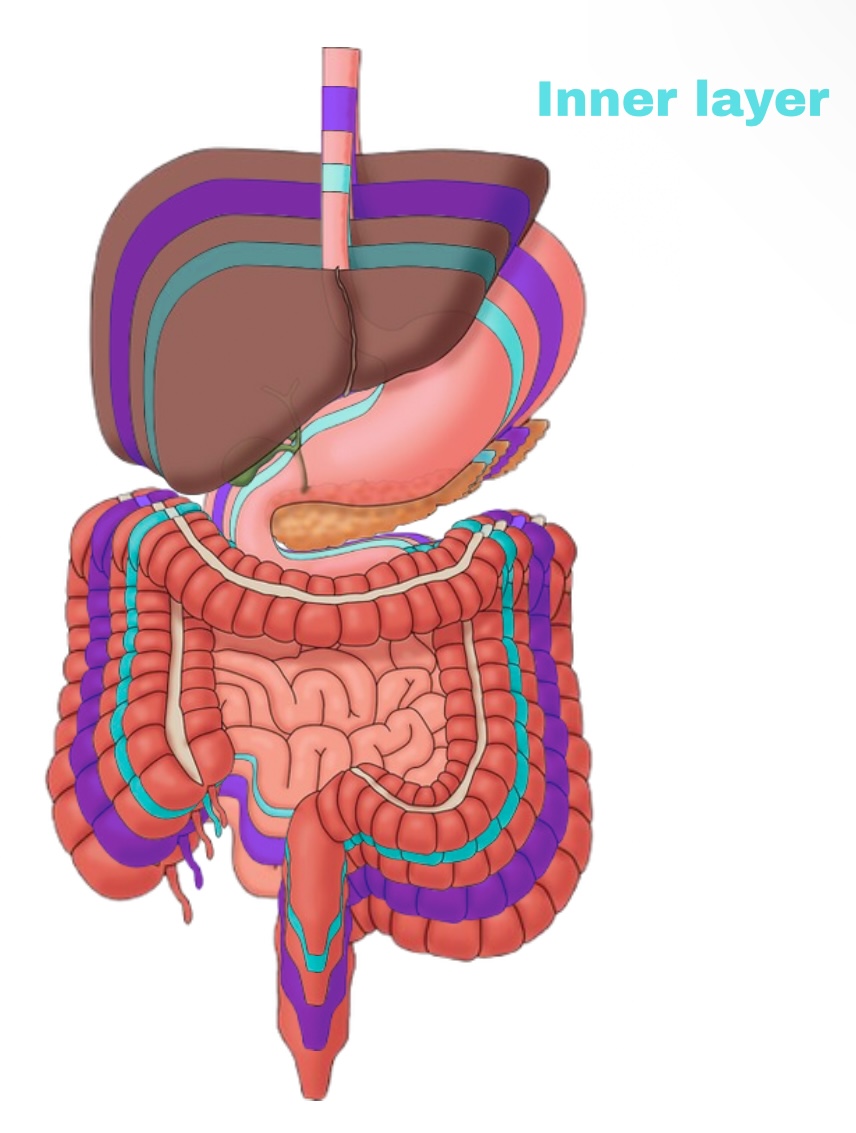

Visceral Peritoneum

Deep layer (surface of organ)